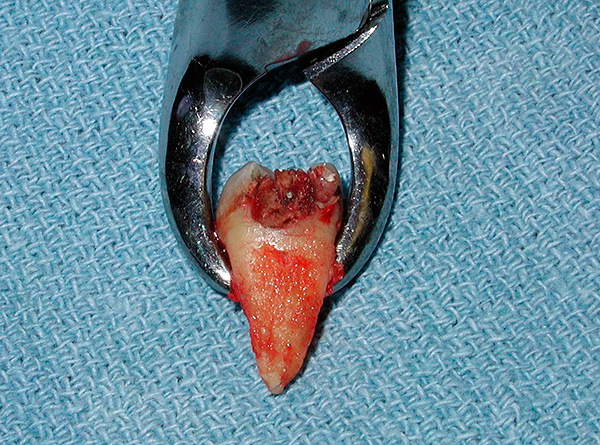

A foto abaixo mostra um exemplo de um dente da frente quebrado a ser removido:

A natureza da preparação depende dos recursos de manipulação futura (com ou sem anestesia, com ou sem sedação), mas as etapas mais básicas incluem: